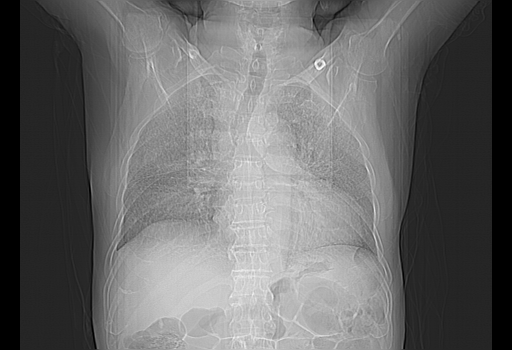

今天复查肺部CT,发现双肺广泛磨玻璃样改变。所以我把3月19日和5月9日相隔50天的肺部CT上传。请大家会诊。

2009年3月19日肺部CT片。

5月9日肺部CT(在4月27日齐鲁医院肺部CT描述部分肺组织磨玻璃样改变,12天后肺组织广泛磨玻璃样改变)

大致读了系列胸部CT:纵隔窗无明显异常,肺窗:从4、27至今:主要是双肺中下野外带可见毛玻璃样改变,目前处于急性肺泡炎阶段,至于原因考虑1、结替组织或胶原血管性疾病所致?2、恶性疾病如恶组在肺部所致的表现或细支气管肺泡癌?3、药物或其它原因如肺蛋白沉着症所致肺泡炎目前不太可能?总之,明天就去请我院的呼吸科、感染科、血液科和临免专家会诊哈。